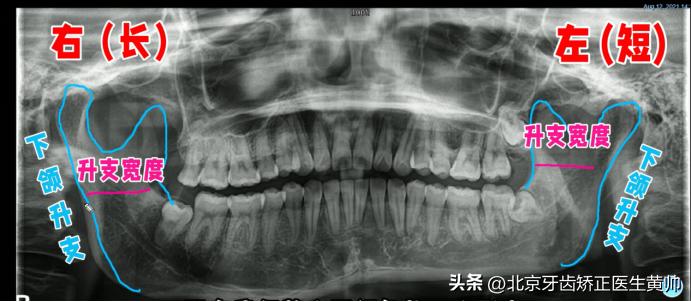

2、曲面断层片

曲面断层片主要看这几个信息:下颌升支的长度、下颌升支的宽度、下颌角的形态。

◆ 下颌升支的长度、宽度是否一致

通常来说我们下颌升支的长度、宽度是基本对称的,视觉上不会存在明显不对称问题。

如果说两侧下颌升支的长度、宽度不一致的问题,那就非常有可能会出现大小脸的情况。

例如这个患者,他右边的下颌升支要长一点,左边的则要稍微短一点。

◆ 下颌角的形态是否一致

从片子上看下颌角双侧发育是不是对称的,以及下颌边缘是否在同一高度。

图中的患者,他的左侧、右侧明显没有在一个水平面上。

所以,如果你的片子当中存在下颌升支的长度、宽度不一致,包括你的下颌角形态发育不对称、下颌边缘线不在一个水平面的问题,这都提示你的大小脸是有骨性因素的。